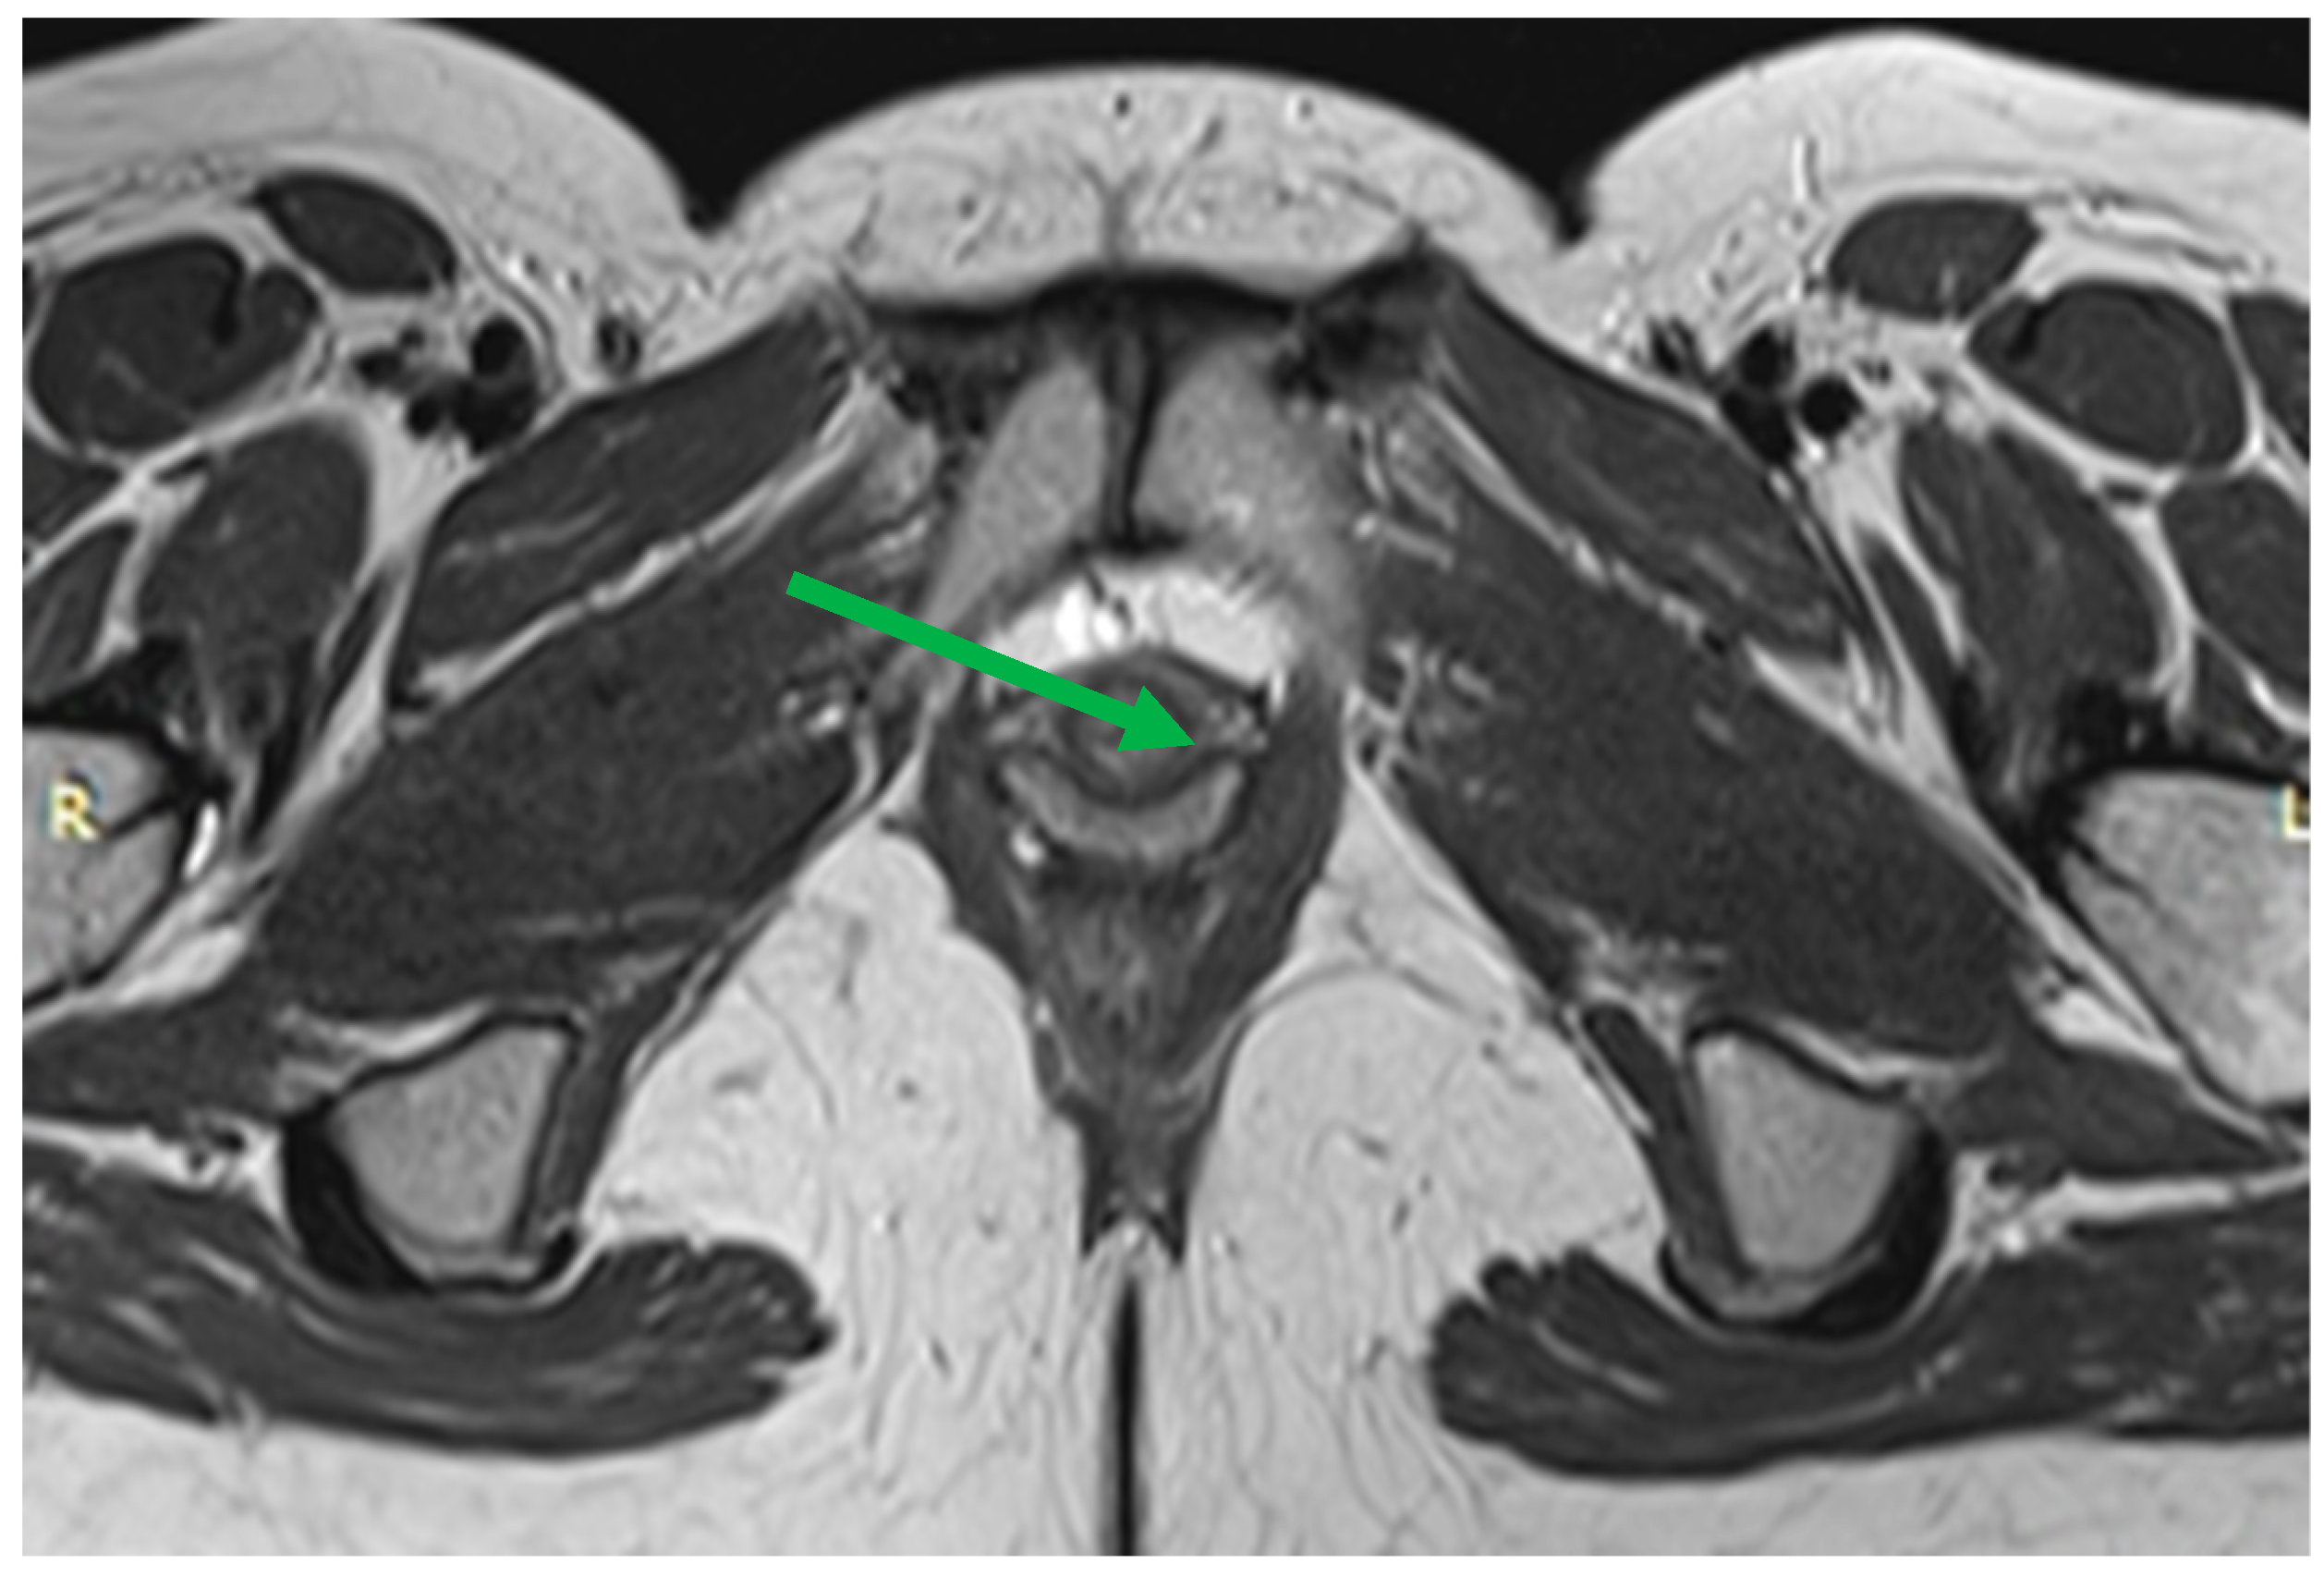

Normal urethra looks like a “target” on axial T2-WI. The mucosal and submucosal layers are characterized by high signal intensity, the transverse striated muscle layer is hypointense, and the middle smooth muscle layer is hyperintense (Figure 7). Shortening of the urethra and insufficiency of its sphincter can be assessed by dMRI. Patients usually have stress urinary incontinence similar to that of UH. When the urethra is less than 3 cm in length, it can be seen to be shortened on MRI scans [50].

Figure 7. Normal urethra (arrow) on axial T2-WI: The mucosal and submucosal layers have high signal intensity, the transverse striated muscle layer is hypointense, and the middle smooth muscle layer is hyperintense. Thinning of the transverse striated urethral sphincter muscle is also associated with urinary loss [51], although the relationship is debated [52,53]. Weakening of the urethral sphincter can lead to urethral diverticulum formation (Figure 8). These changes can manifest as urethral obstruction, followed by infection of the paraurethral glands. Diverticula can vary in size, with the larger ones looking like a fluid-filled pouch surrounding the urethra. To make this diagnosis, it is sufficient to perform a normal MRI examination without performing functional tests with pressure.